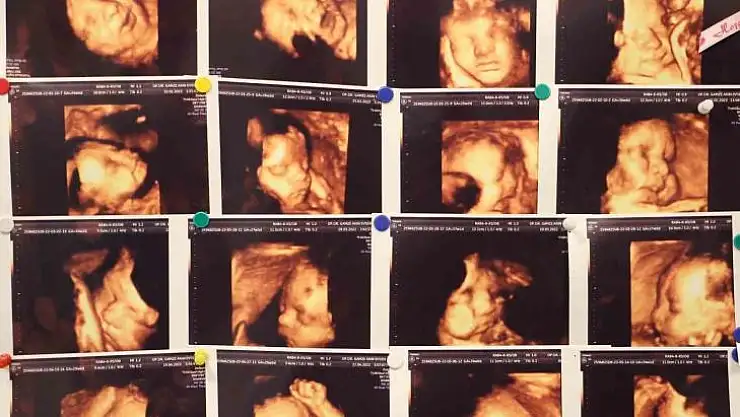

Memorial Hastanesi Kadın Hastalıkları ve Doğum Uzmanı Op. Dr. Gamze Akın Evsen, çocuk sahibi olmaya hazırlanan çiftlerin yaşadığı en büyük travmalardan biri olan gebelik kayıpları, çoğu anne adayının psikolojisinin bozulmasına ve çaresizlik hissine kapılmasına neden olduğunu belirterek, "Klinik olarak saptanan gebeliklerin yüzde 10-15’i düşükle sonuçlanmakla beraber bu durumun tekrar etmesi yani tekrarlayan gebelik kayıplarında oran Yüzde 3 ila 5’tir" dedi.

Tıbbi literatürde abortus yani düşük olarak tanımlanan gebelik kaybı, bebeğin 500 gram ağırlığına ulaşmadan veya 20’inci haftadan önce çeşitli sebeplerden ötürü gebeliğin sonlanması anlamına geldiğini açıklayan Dr. Evsen, genelde en sık ilk 3 aylık dönemde görülebilmekte olduğunu dile getirdi.

"Klinik olarak saptanan gebeliklerin yüzde 10-15’i düşükle sonuçlanmakla beraber bu durumun tekrar etmesi yani tekrarlayan gebelik kayıplarında oran Yüzde 3 ila 5’tir. Tekrarlayan gebelik kayıplarında en sık kromozomal sıkıntılar olmakla beraber, genetik anomaliler, hormonsal sıkıntılar, kan pıhtılaşması, rahmin yapısal bozuklukları, annede var olan diyabet ve guatr gibi sistemin hastalıklar, annede tekrarlayan enfeksiyonlar, bağışıklık sistemi sorunları ve çevresel faktörler görülebilmektedir."